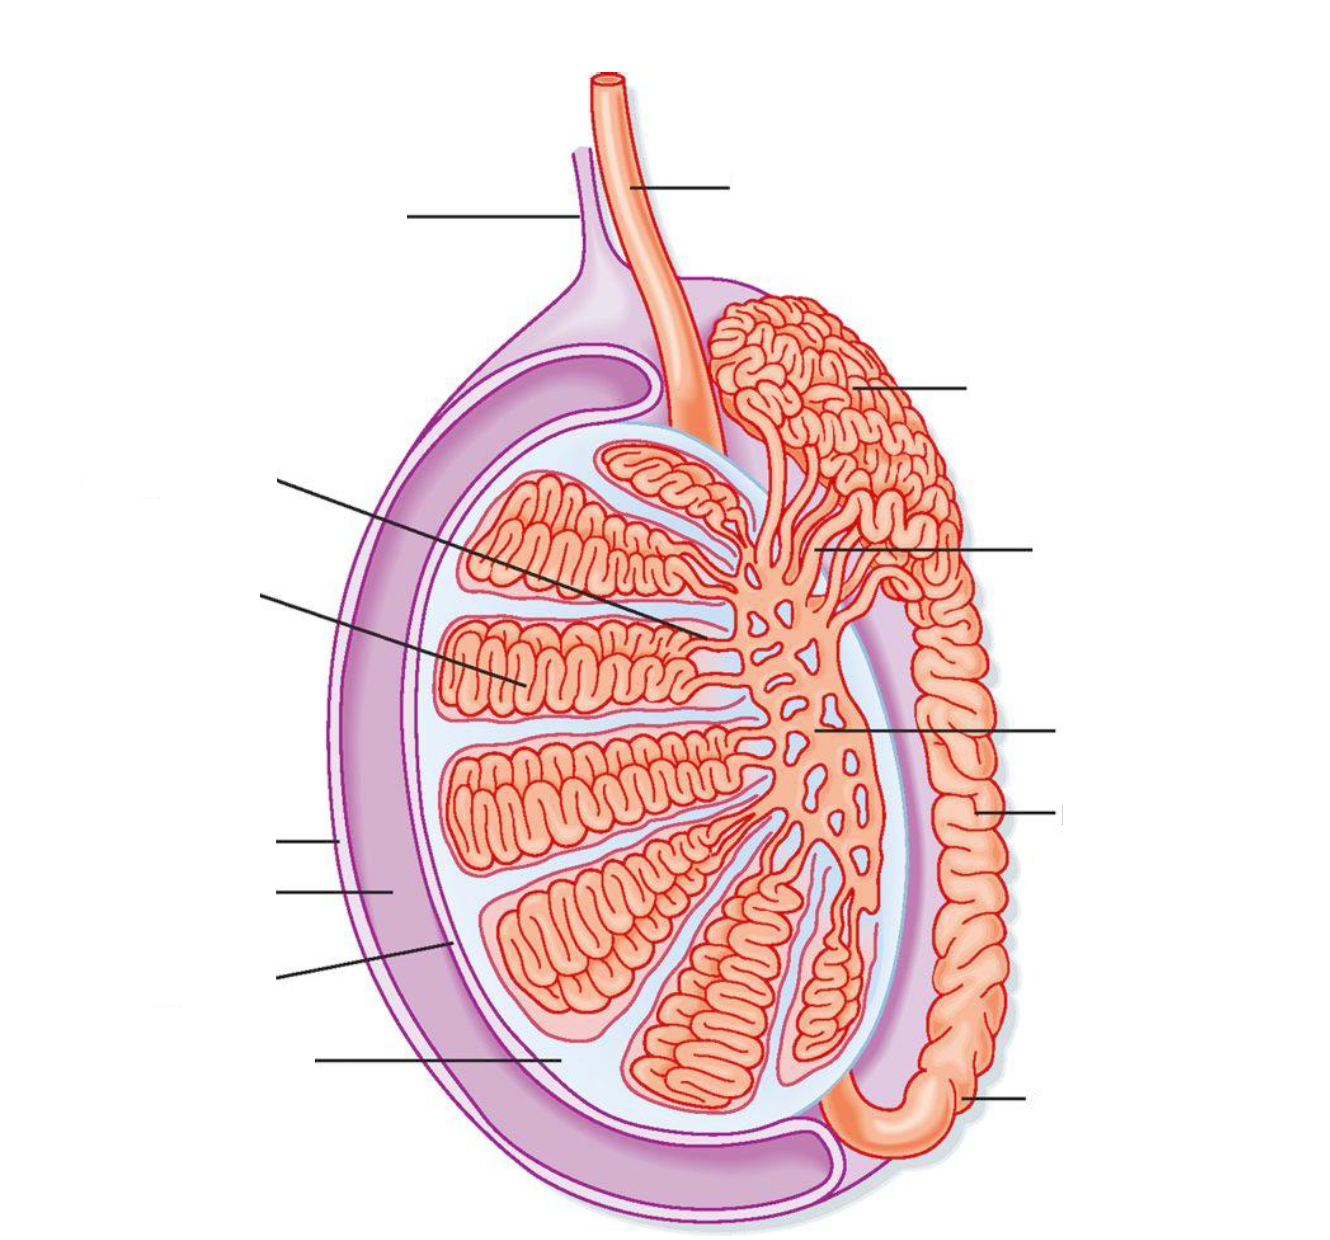

Where does spermatogenesis occur?

Intratubular compartment of seminiferous tubules

Seminiferous tubules are contained by […]

Perytubular myoid cells

Leydig Cells

Sertoli Cells

After production in the seminiferous tubules, sperm travel next to the […]

Epididymis